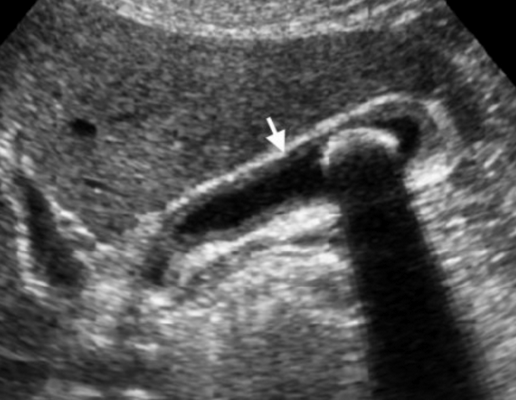

УЗИ хронических холецистит

Термин хронического холецистита используют для обозначения вялотекущего воспалительного процесса с фиброзированием стенки желчного пузыря и образованием в просвете камней.

Представлен больной с хроническими болями в правом подреберье, который ежедневно воздерживался от еды с вечера. Утолщение слабо выраженное и не является физиологическим. Также визуализируются обструкция и камень. После УЗИ данному больному был поставлен диагноз — хронический холецистит.